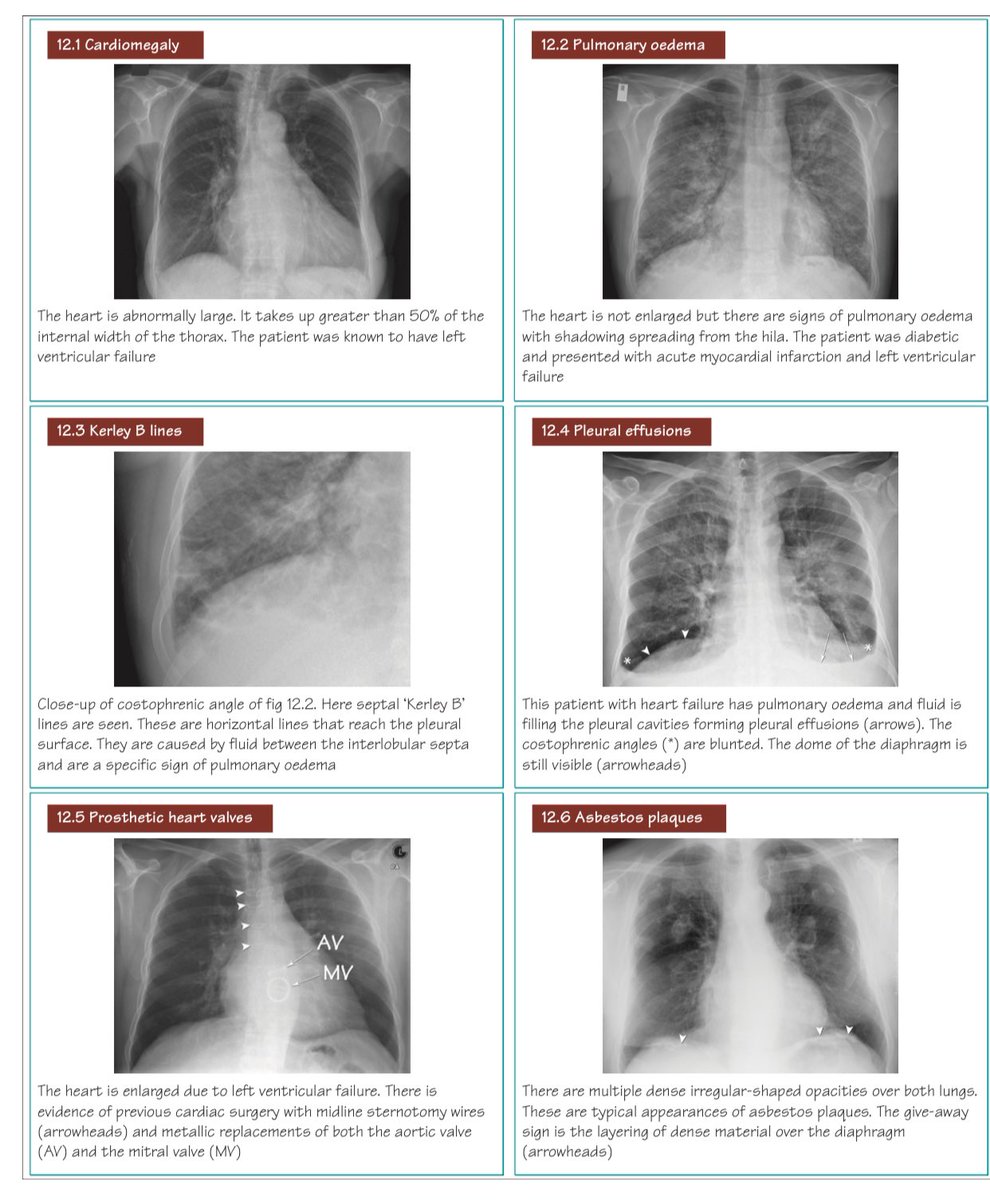

تصوير الصدر بالأشعة السينية من أول الإجراءات التي تخضع لها في حال اشتباه إصابتك بمرض في القلب أو الرئة لا سمح الله

هام جدا☢️

الأمراض الصدرية وكيفية تمييزها على صور الأشعة الأشعة السينية 👇🏼

CXR classic cases